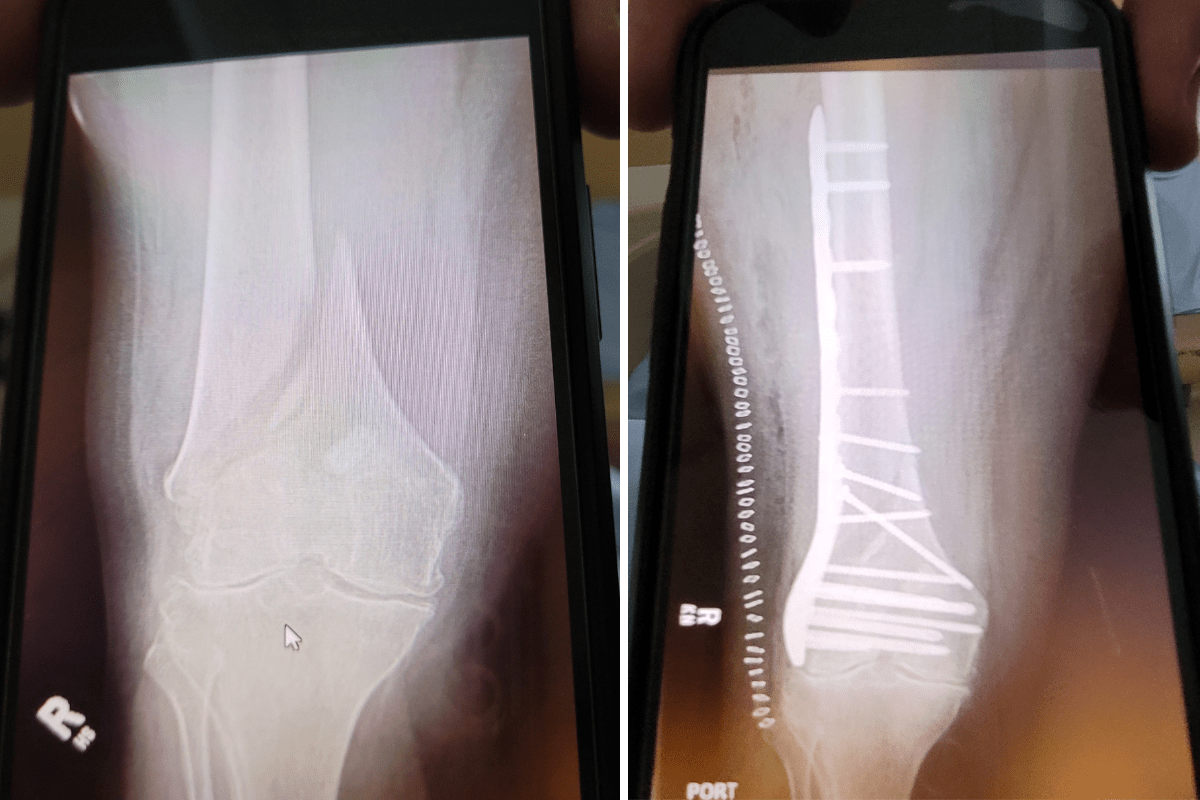

X-ray image of Tammy Vande Wiel’s femur fracture before, left, and after surgery, right.